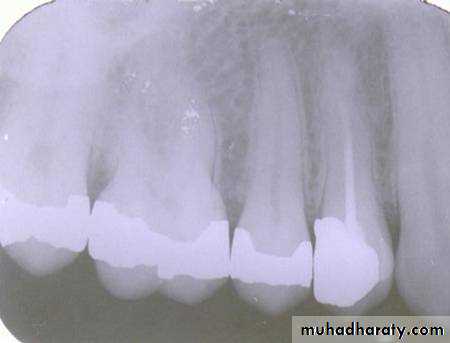

Is the composite restoration on tooth # 8 (arrows) located on the buccal or lingual?

canine filmincisor film

The restoration is located on the buccal. The tube head moves mesially from the canine film to the incisor film (x-ray beam projected more distally) and the composite moves distally, which is the opposite direction.